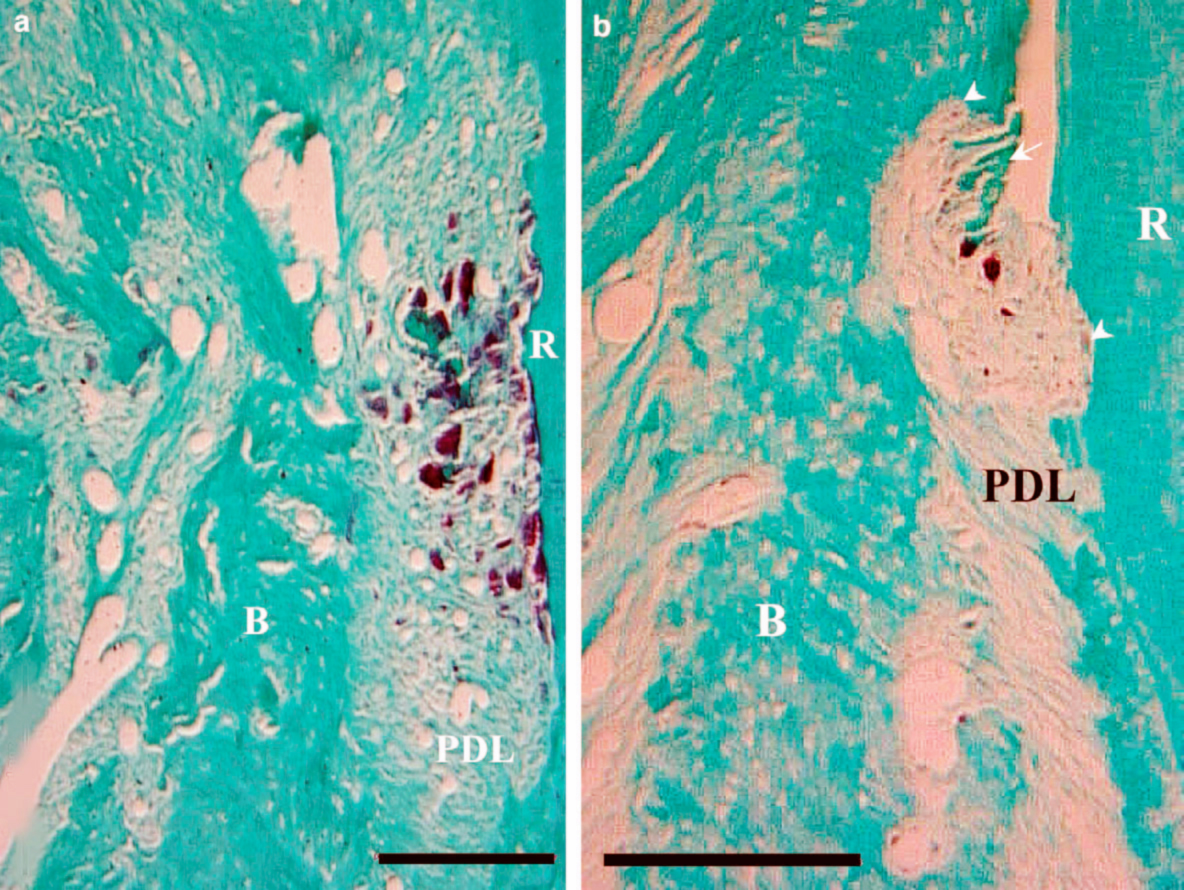

Alveolar bone resorption was inhibited in a ligationinduced Alveolar Bone Resorption alveolar ridge preservation (arp) is a method of decreasing bone resorption following tooth extraction and. alveolar bone reshaping is a surgical procedure that corrects alveolar bone morphology to a physiological form without removing the native. alveolar bone loss is a hallmark of periodontitis progression and its prevention is a key clinical challenge in periodontal. bone resorption. Alveolar Bone Resorption.

Orthodontically induced root and alveolar bone resorption Inhibitory Alveolar Bone Resorption alveolar ridge preservation (arp) is a method of decreasing bone resorption following tooth extraction and. this article reviews recent research into mechanisms underlying. alveolar bone loss is a hallmark of periodontitis progression and its prevention is a key clinical challenge in. alveolar bone loss is a hallmark of periodontitis progression and its prevention is a key. Alveolar Bone Resorption.